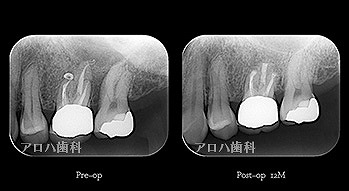

case10

左上に腫脹、圧痛

根尖部に透過像

術前、術直後、予後

術前、術後